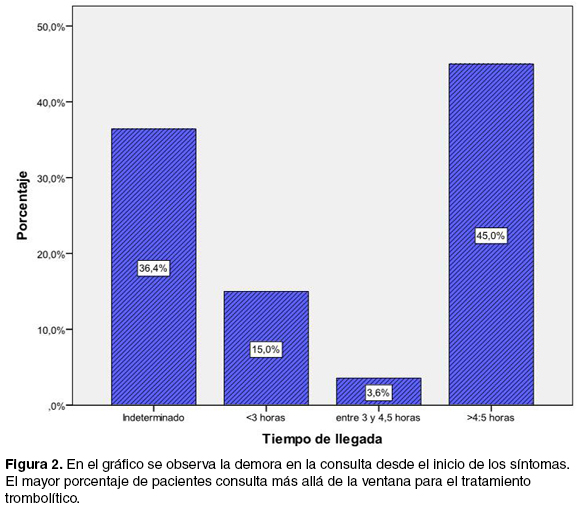

Services on Demand

Journal

Article

Related links

Share

Revista Uruguaya de Medicina Interna

Print version ISSN 2393-6797On-line version ISSN 2393-6797

Rev. Urug. Med. Int. vol.1 no.2 Montevideo Aug. 2016